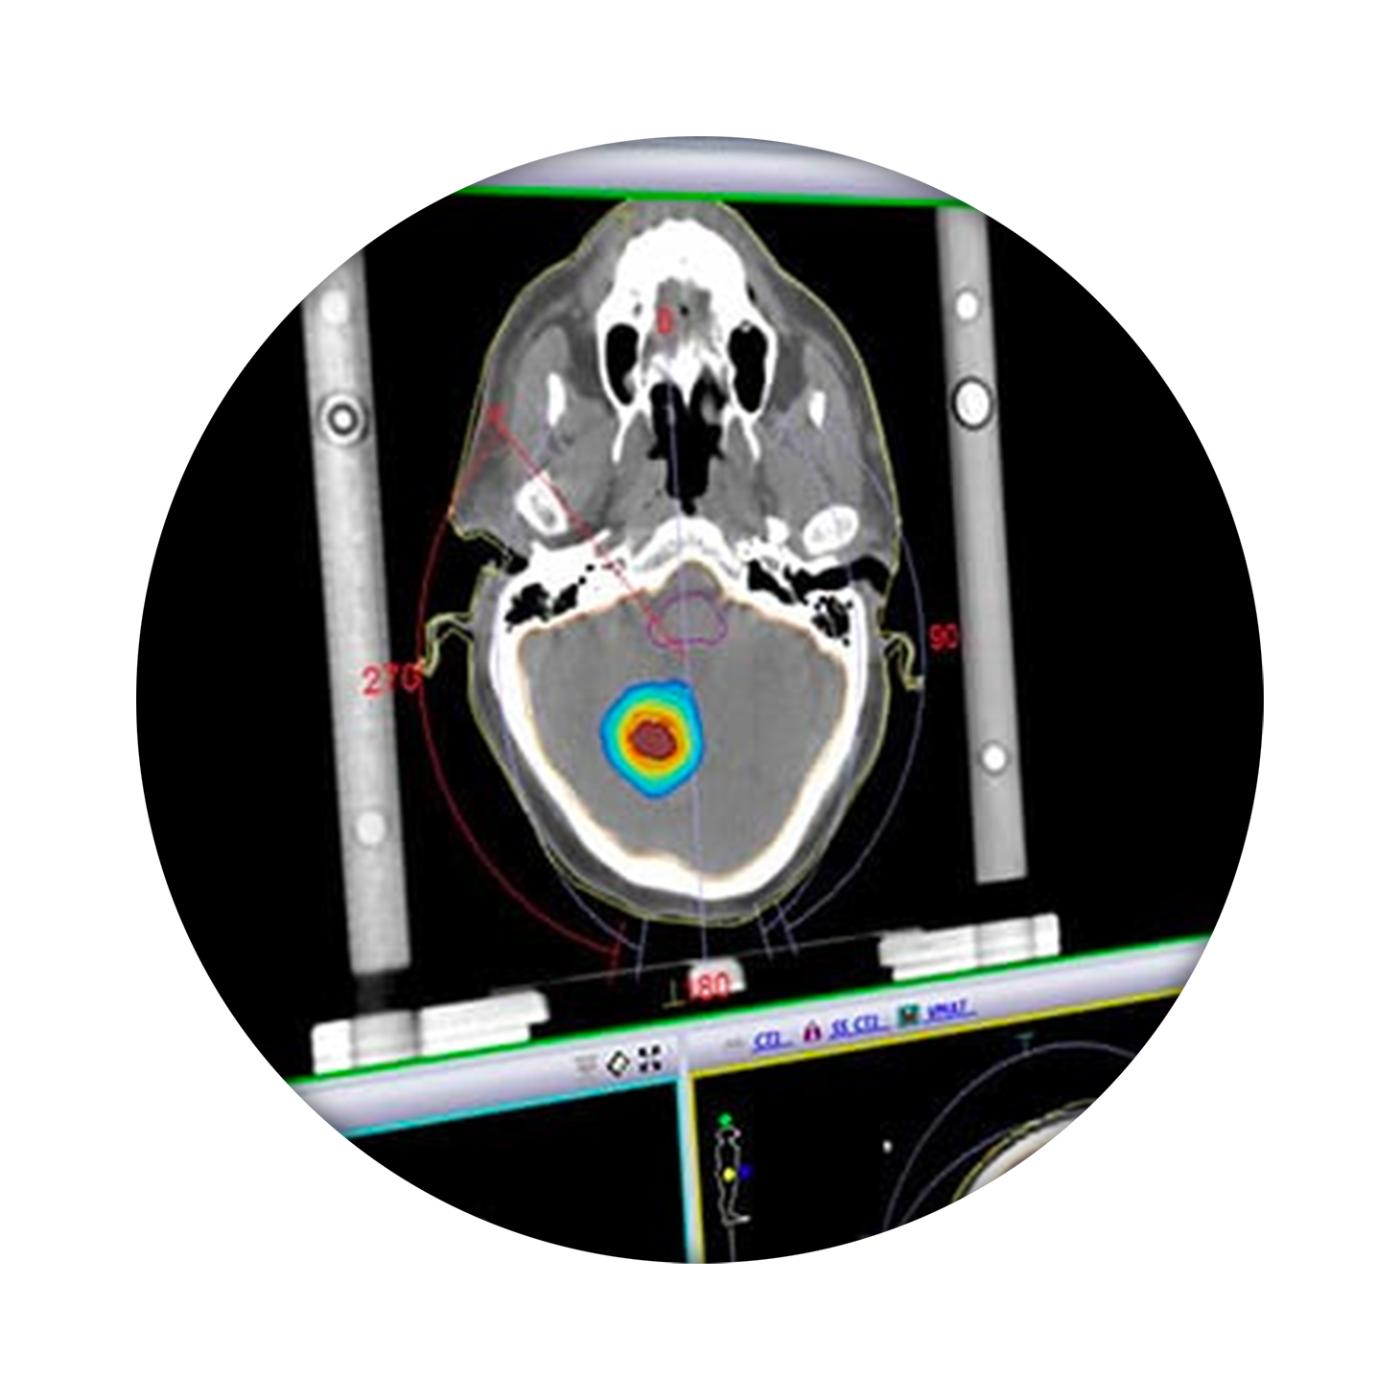

我科 Elekta Monaco 治疗计划系统 发布时间:2018/7/4 6:39:00       浏览次数:4890次

Monaco帮助临床医生提供最高标准的治疗。利用生物智能和标准化的计划解决方案,Monaco帮助临床医生了解患者生物学状态,同时提供快速有效的计划设计方案,将优化后的计划提交到治疗流程。